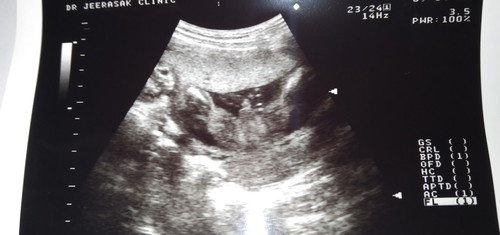

มีใครให้ชัดกว่านี้มั้ยค่ะแม่ 21w4d กำหนดคลอด23สิงหาคม ขอดูแม่ๆที่คลอดสิงหาคมหน่อยจ้าได้เพศไหนกันบ้างเอ่ย??